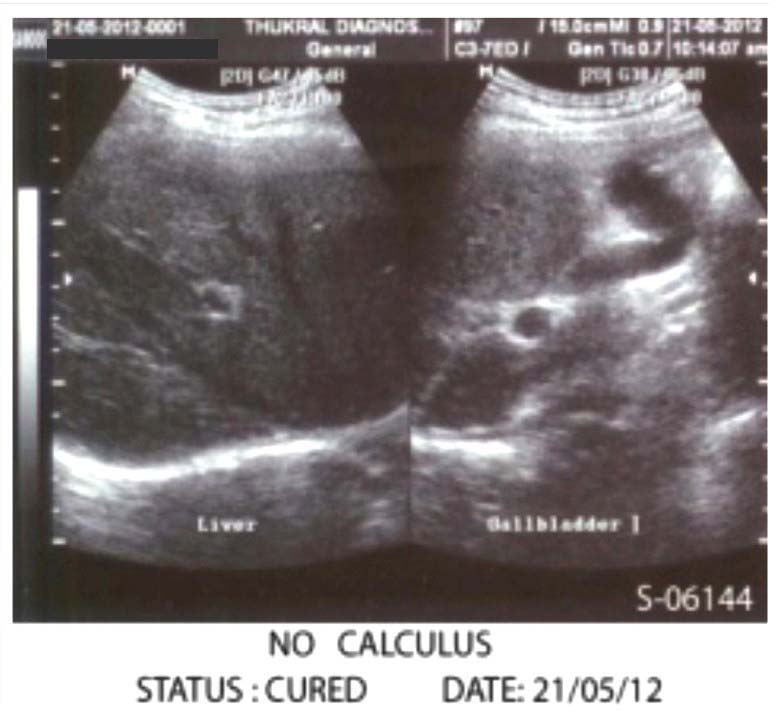

After 4-5 months ultrasonography Reports showed gall bladder is not well distended however normal in shape, position and outline. No calculus or mass lesion is seen.

After Treatment